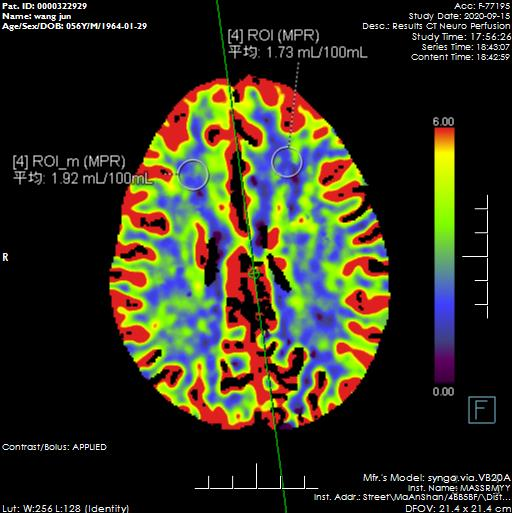

CTP檢查:左側(cè)額葉及基底節(jié)區(qū)異常灌注,考慮腦梗、腦缺血。